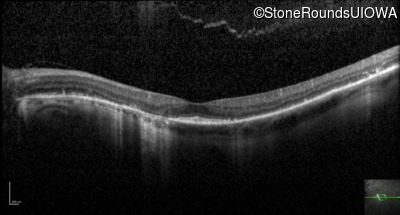

Optical Coherence Tomography - Right - 20/20 -2

Exemplar / OCT Stack